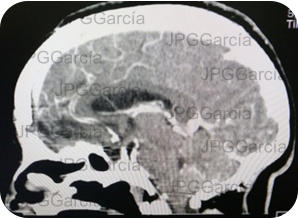

Tomografía contrastada corte sagital mostrando remoción de la lesión tumoral